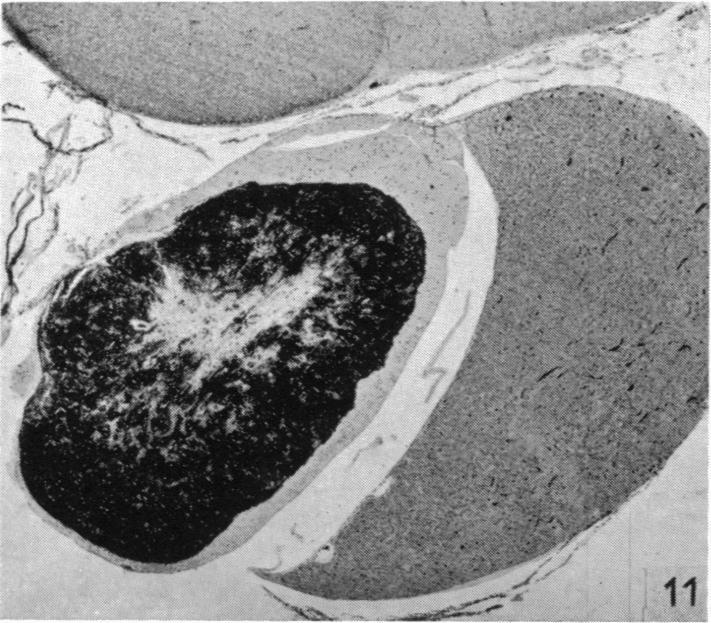

Hypothalamic neurosecretion in the dog and cat, with particular reference to the identification of neurosecretory material with posterior lobe hormone.

J Anat. 1955 Jul;89(3):301-16.